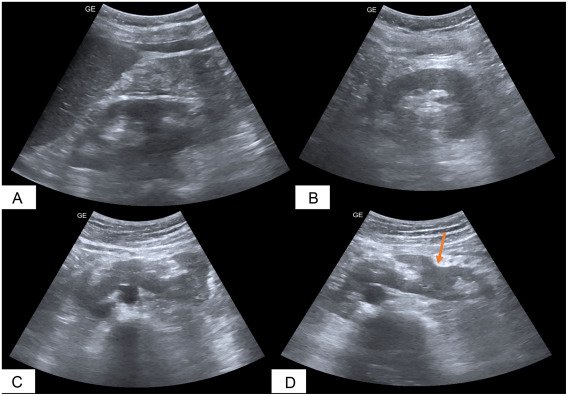

The patient, a 63-year-old man with no significant medical history, presented with persistent pain in the left lumbar region. Ultrasound examination revealed a central horseshoe kidney and two additional kidneys in the left renal fossa, which appeared partially fused, raising suspicion of a complex congenital anomaly. All kidneys showed preserved function, with a few non-obstructive stones (they don’t block the flow of urine, but they can cause infections). Treatment was conservative, including analgesics, hydration, and advice to prevent stone formation. After six months of follow-up, the patient remained completely symptom-free, with stable kidney function.